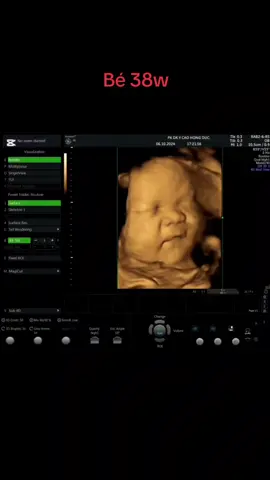

Bé 38w #DrHieuycaohongduc #ycaohongducyb #sieuamthai #xuhuong